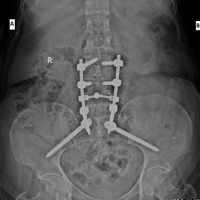

Based on clinic-radiological findings, a provisional diagnosis of osteochondroma arising from D12 vertebrae was made and planned for excisional biopsy. Under general anesthesia, the patient was placed in the prone position (Fig. 2). Around 6–7 cm of midline incision was placed at the D11-D12 region. Deep fascia was cut in the midline in line with the skin incision. Rather than subperiosteal elevation of paraspinal muscle, the tumor was approached through the left paraspinal muscle to remain extra-periosteal while excising the tumor (Fig. 3). En bloc excision of the tumor was done (Fig. 4). The small amount of stock was nibbled off till it felt flat over the lamina. The wound was irrigated and closed in layers. The final subcuticular skin suture was applied for cosmesis (Fig. 5). The patient was mobilized on the next post-operative day.